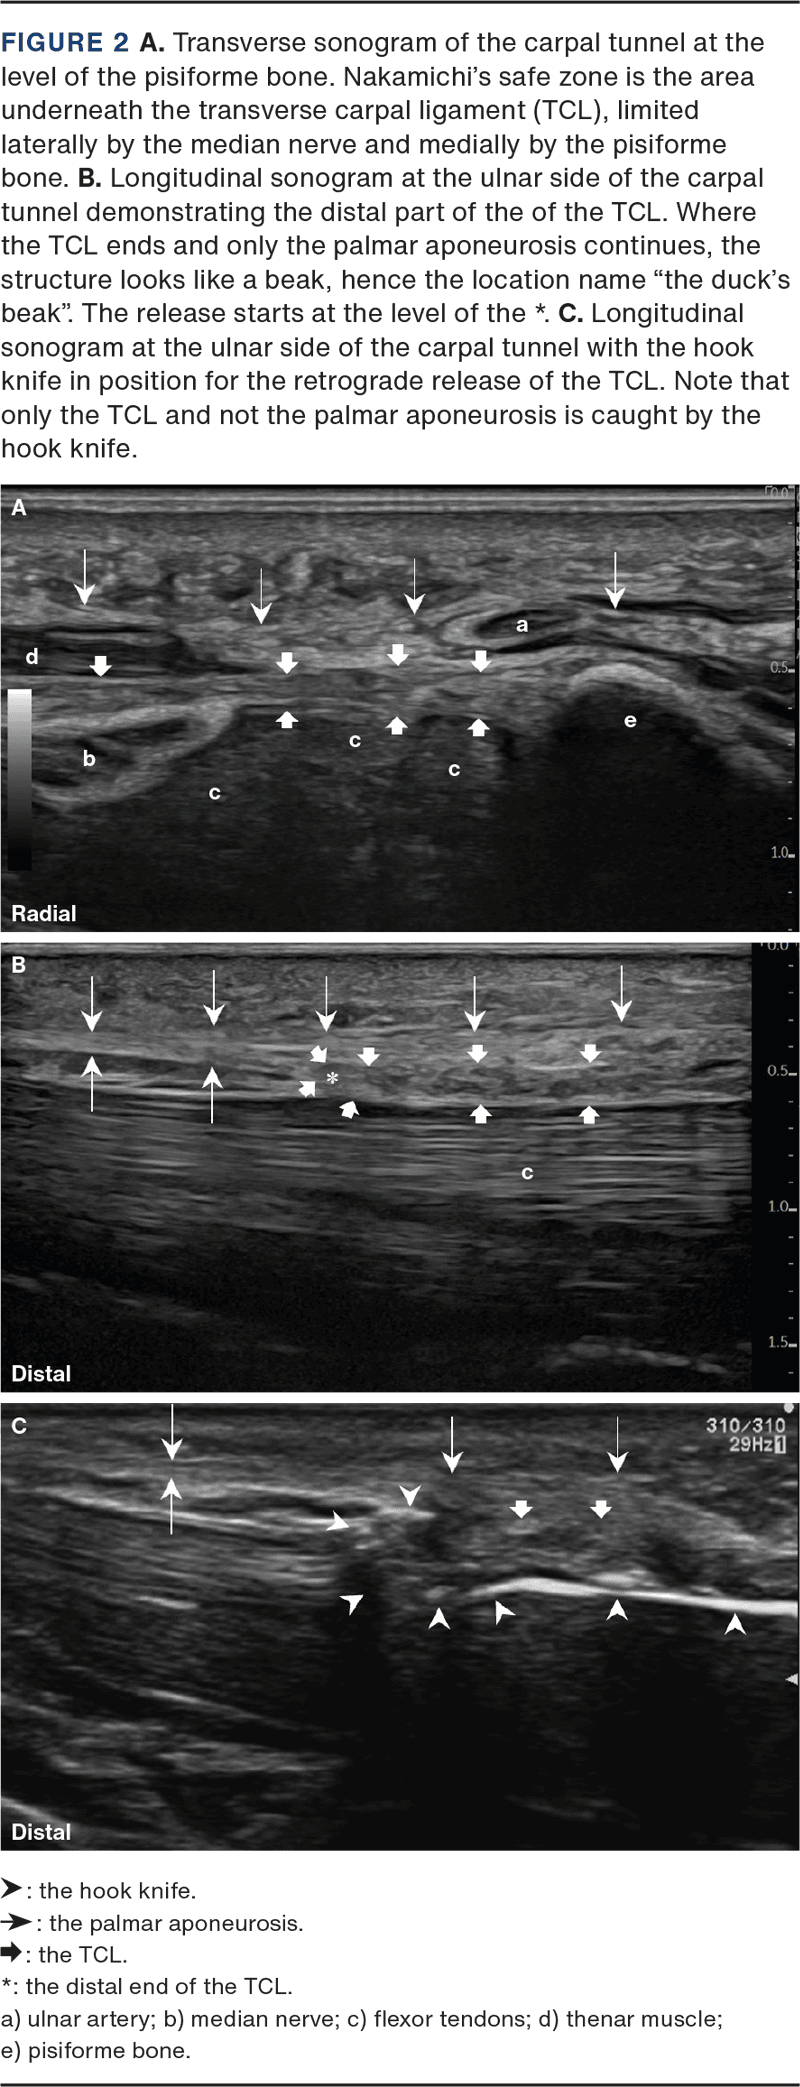

During the preoperative US, the carpal tunnel was assessed prior to the UMIU-CTR to identify the landmarks needed to perform the intervention, anatomic variations (like a bifid median nerve) and unexpected nerve branches/small vessels (like a looped thenar motor branch), see Figure 2A and B. US intervention details are described in Supplementary Material Appendix A, pages 2-5.